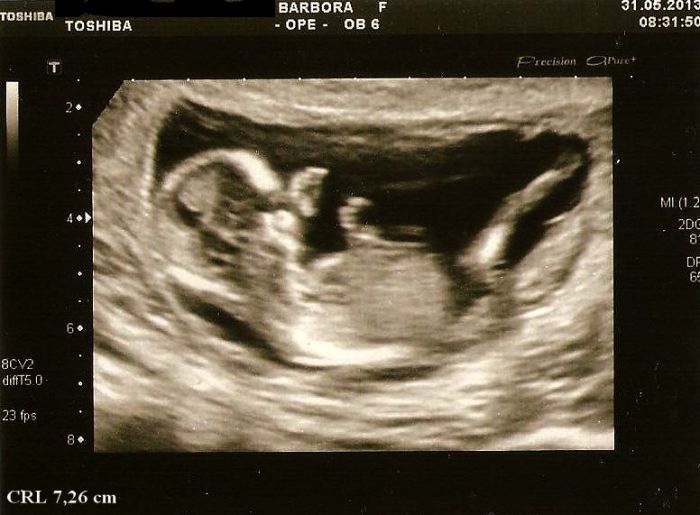

Pak ho trošku poškádlila, tak zaujal normální polohu a mohli jsme měřit. CRL máme 7,26cm a odpovídáme 13+3tt, projasnění bylo 1,3, takže prý v pořádku a stehenní kostička meřila 1 cm..Dr.mi všechno krásně popisovala a přibližovala, hlavně na obličejíčku a mrňous u toho sebou aktivně mrskal a ukazoval nám jak má dlouhý nožičky a pak se dr. smála a říká,,a teď si cpe ručičky do pusinky''..

Přikládám 2 fotečky mrňouska,na té jedné se musím smát jak ukazuje chodidlo a druhou nohou se snaží prokopnout ven z bříška